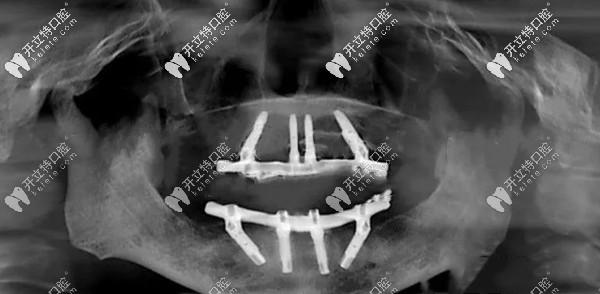

我牙槽骨缺失做全口種植牙的效果

上面是我做完全口種植牙后3個(gè)月,拍的CT片▲